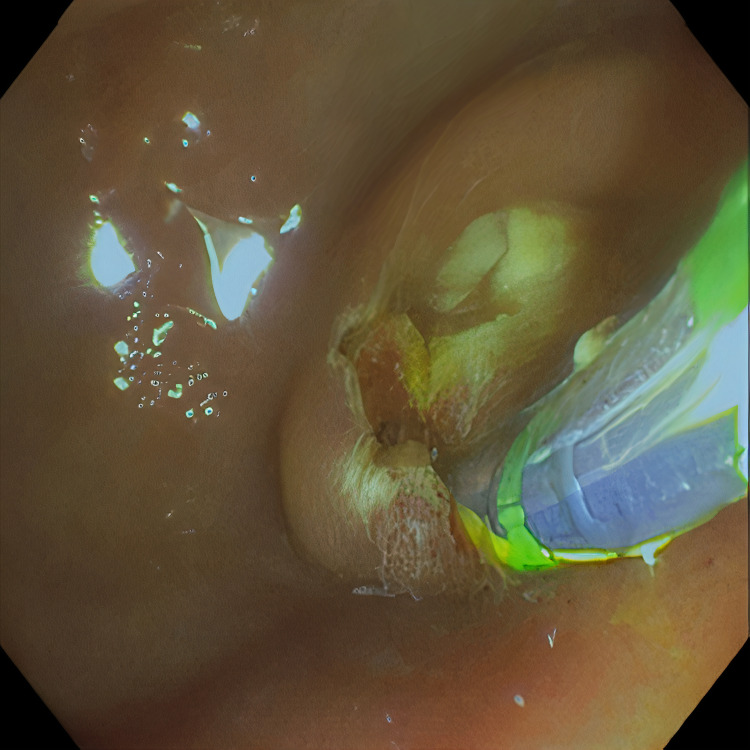

Pertinent labs include elevated white blood cells (13.5×10³/µL), total bilirubin (15.7 mg/dL), direct bilirubin (11.7 mg/dL), aspartate aminotransferase (98 U/L), and alanine aminotransferase (41 U/L). Urinalysis showed tea-colored urine. CT scan of the abdomen and pelvis revealed a collapsed gallbladder with CBD obstruction and bile duct dilation consistent with chronic inflammation. Endoscopic retrograde cholangiopancreatography (ERCP) was then performed which demonstrated cystic duct stone eroding into the common hepatic duct, hence the diagnosis of Mirizzi syndrome was made. Cholangioscopy confirmed the eroding stone, chronic inflammatory changes, and destruction of the bile duct. A cholecystoduodenal fistula with pus drainage was noted in the duodenal bulb. The patient was diagnosed with MS type V according to the ERCP findings. The stone was not amenable to endoscopic removal, but stone debris, clots, and pus (Figures 1–4) were swept. He was referred to the surgical team for cholecystectomy and repair of cholecystoduodenal fistula.